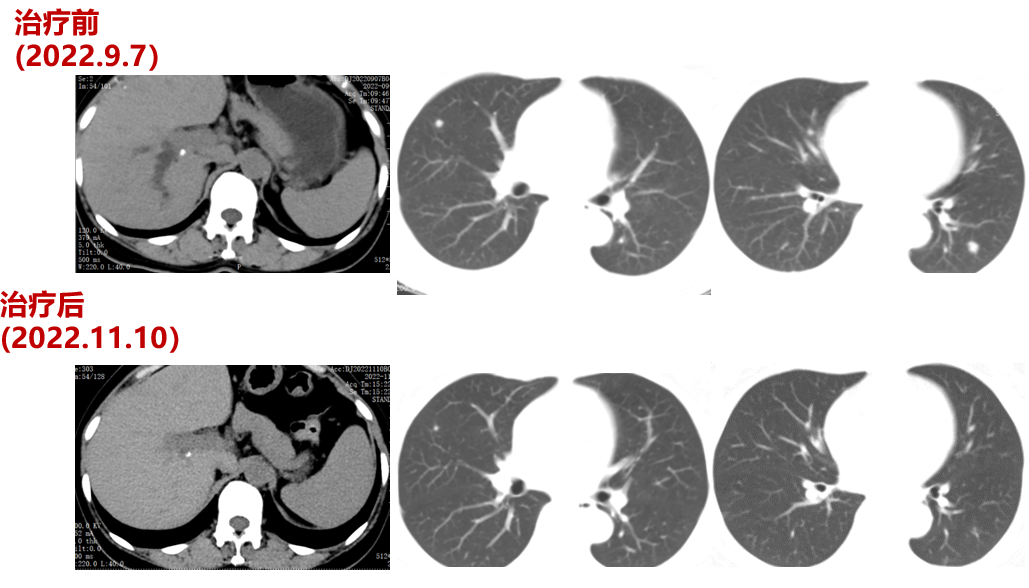

2022-09-07至2023-01-03院外使用DS-8201治疗5周期。2周期后疗效评价:PR。CT示:腹膜后淋巴结较前部分缩小;双肺多发转移灶较前缩小。